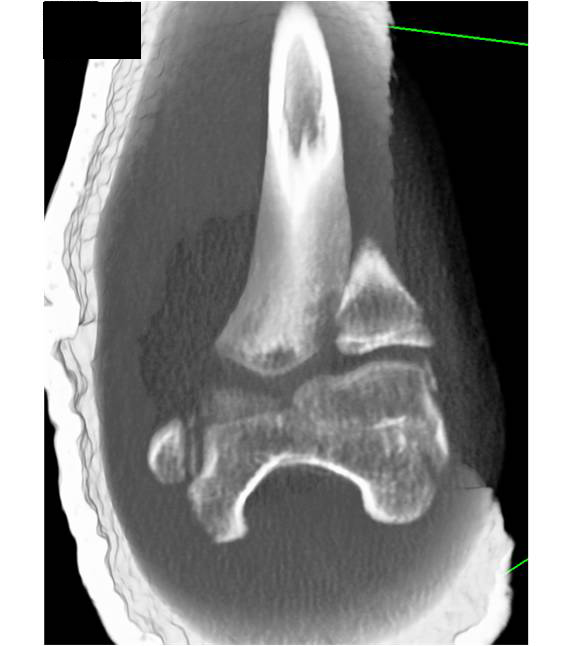

Coccyx Fractures